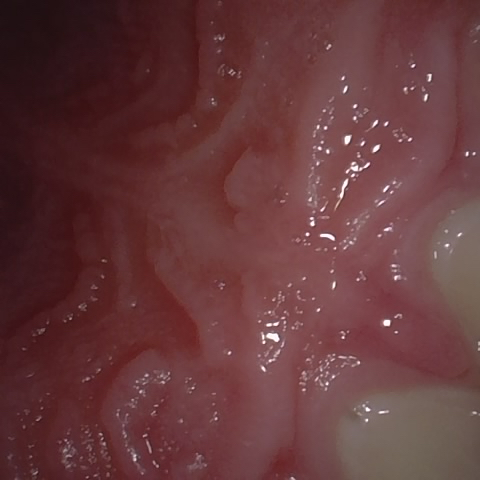

NHD39990

Annotated as "Good"

Original Image Rendering Image